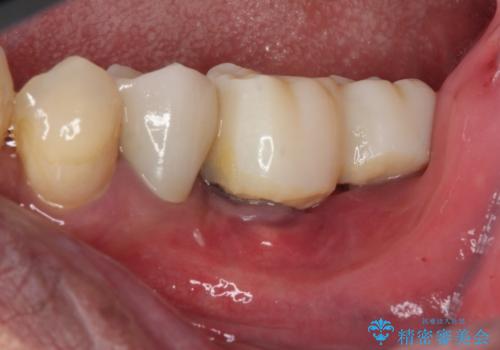

インプラント埋入後、手前のインプラント周りの丈夫な歯肉(角化歯肉)が失われてしまったため、角化歯肉の移植を行うこととなりました。